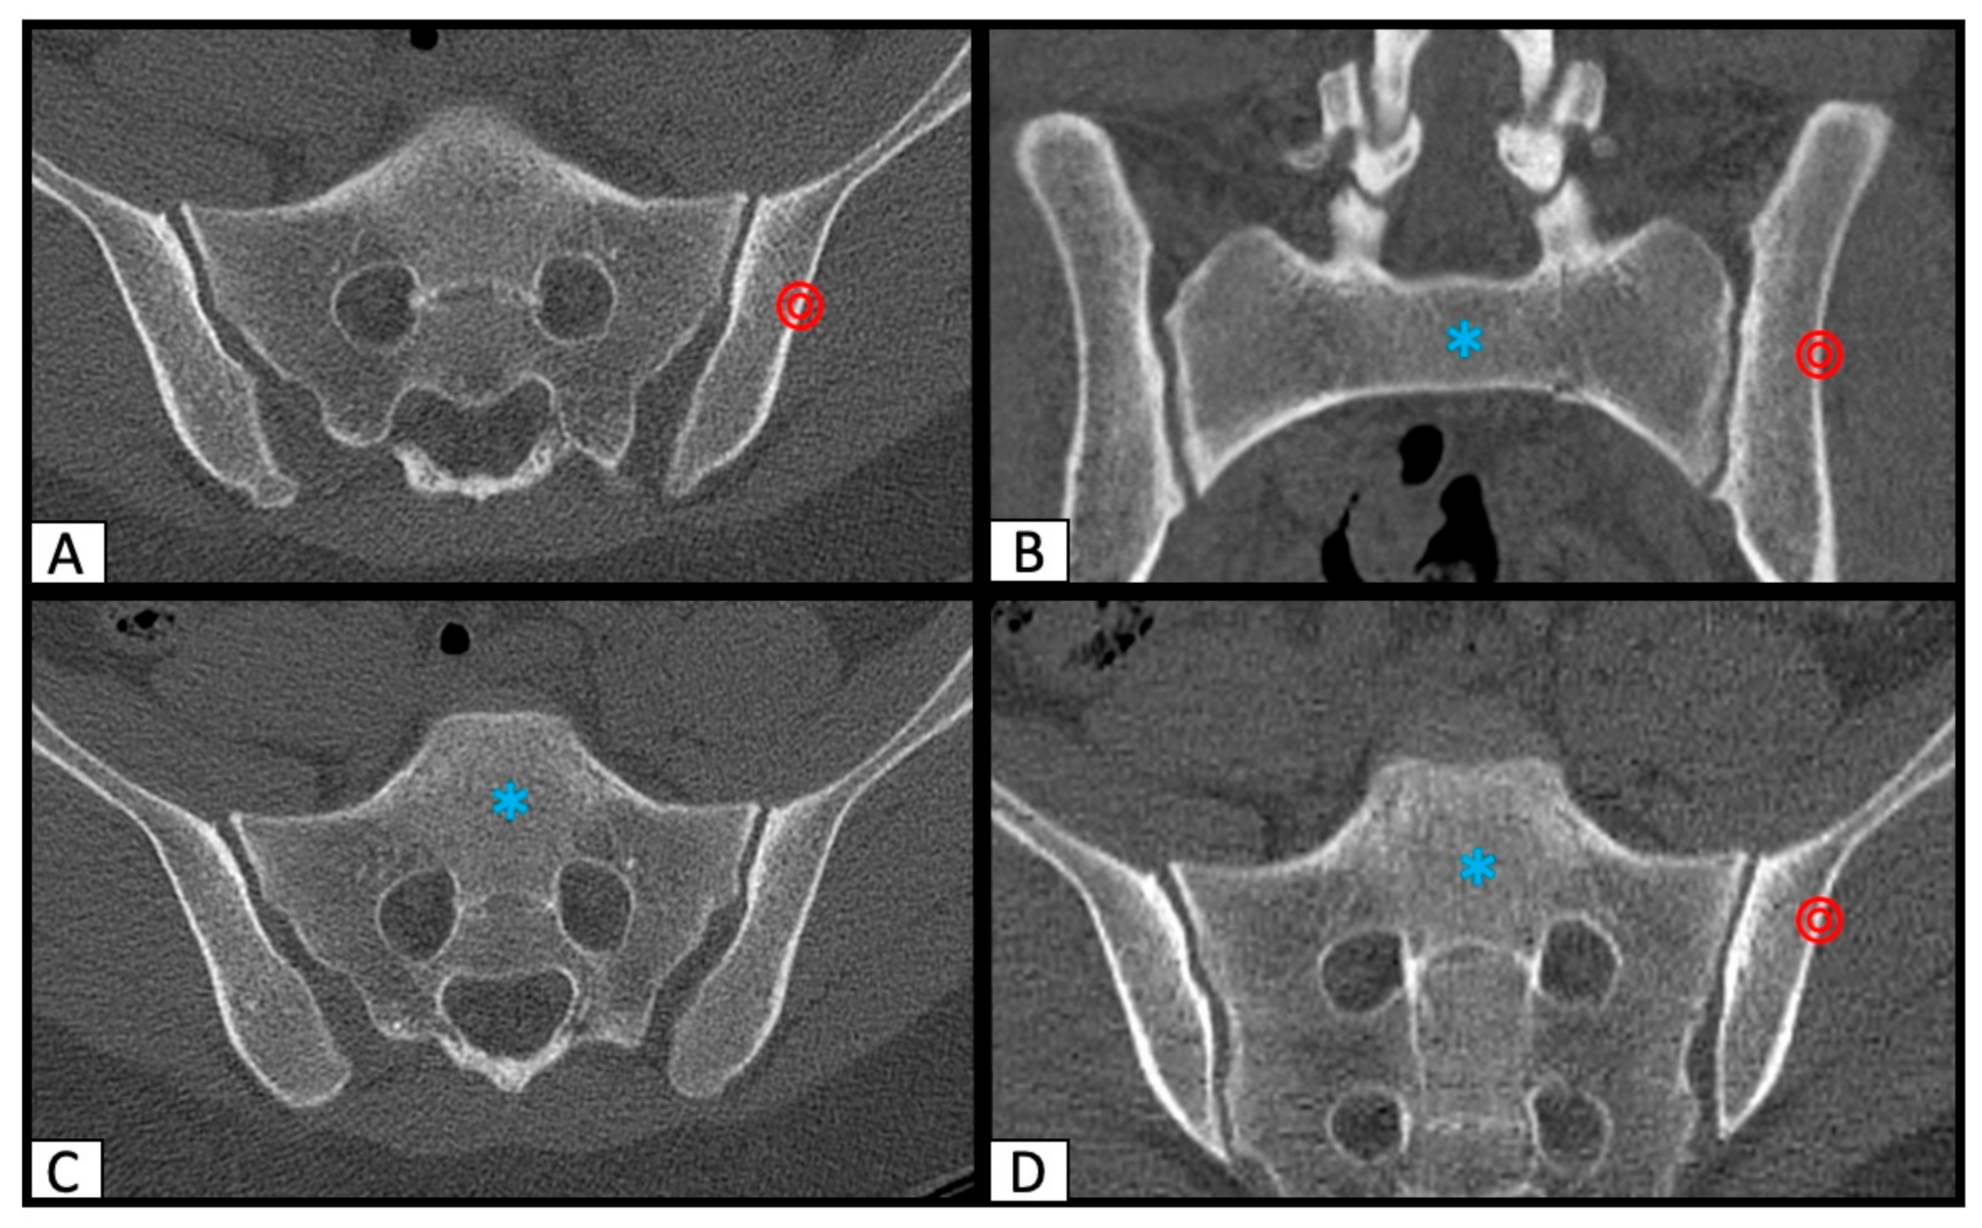

2.1. Determination of SI Screw Corridor

2.2. Image Processing with the Slice Fusion Method